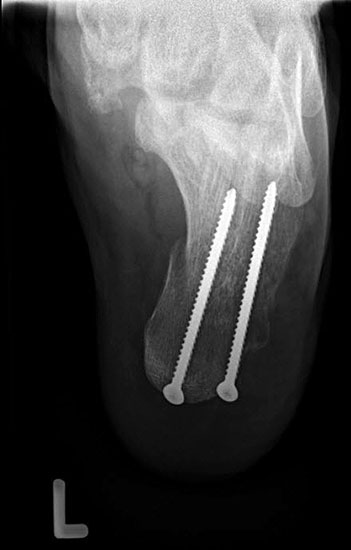

Stadium IV – komplette Rückfuß-Arthrodesen

- TTC- / pantalare Arthrodese

Im Stadium IV der (fixierten) Planovalgus Deformität und lateral betonter OSG-Arthrose umfaßt die operative Therapie eine korrigierende Arthrodese von OSG und USG-Arthrodese (Tibio-talo-calcanear = TTC Fusion) oder bei Arthrose in der Chopart-Gelenkreihe eine pantalare Arthrodese 5556.

Für die TTC-Arthrodese haben sich retrograde Rückfußnägel bewährt, da sie eine gute Primärstabilität bieten und vergleichsweise wenig Weichteildissektion erfordern. Die Indikation muss aber sehr differenziert gestellt werden, zumal das Gangbild anschließend erheblich eingeschränkt sein wird und Anschlußarthrosen trotz optimaler Schuhversorgung mit Abrollrampe zu erwarten sind. Solange die OSG-Arthrose beschwerdearm bleibt, sollte daher auch eine umfangreiche Korrektur der Planovalgus-Deformität mit Rekonstruktion des Ligamentum deltoideum anstelle der TTC- und pantalaren Arthrodese favorisiert werden 57.